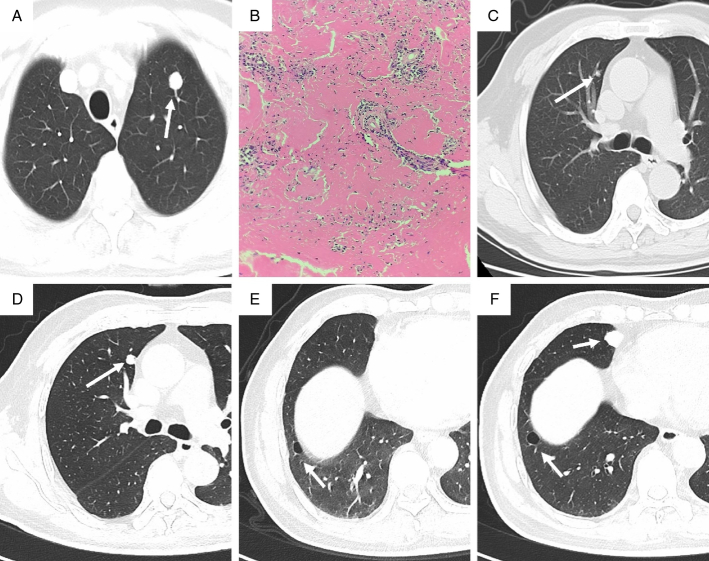

Results: Among the 13 patients, there were 3 males (23.08%) and 10 females (76.92%). Their ages ranged from 37 to 68 years, with a mean age of (57.85±8.40) years and a median age of 59 years. Three (23.08%) patients had cough and sputum, while the others (76.92%) had no clinical symptoms. Before surgery, 6 patients underwent chest CT scans, and NPA changes in size, shape, and density were observed. Six cases (46.15%) were located in the left lung (4 in the upper lobe and 2 in the lower lobe), and 7 cases (53.85%) in the right lung (3 in the upper lobe, 2 in the middle lobe, and 2 in the lower lobe). Seven cases (53.85%) of NPA were round or oval, while 6 cases (46.15%) were irregularly shaped. Out of the NPA cases, 11 (84.62%) were solid nodules with well-defined boundaries, including 2 cases of solid nodules with surrounding calcification. In addition, 2 cases presented as solid nodules with cavities. Ten cases (76.92%) had multiple cystic lesions in the bilateral lungs, in which 7 cases had more than 10 cysts with obvious cyst walls, and 1 case showed a solid nodule on the cyst wall. During the postoperative follow-up, 1 patient experienced an increase in the size of the original nodule and the appearance of new solid nodules. Subsequent surgery revealed mucosal-associated lymphoid tissue lymphoma (MALT). The remaining patients were followed up regularly, and their conditions remained stable.

Conclusions: NPA is more common in middle-aged and elderly people and is more likely to occur in women. Most cases are asymptomatic, and bilateral lungs can be involved. For nodules with multiple pulmonary cysts found by chest CT, the possibility of NPA should be considered, and further histopathologic examination is needed to confirm the diagnosis. Most patients with NPA have a good long-term prognosis after surgical resection, but some patients require further investigation and close follow-up due to underlying causes.